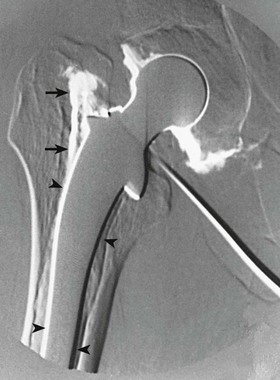

Hip arthrography is most often performed on children in a surgery suite by an orthopedic surgeon. Arthrography is used to evaluate lateral femoral head displacement and after closed reduction to ensure that there is no folding or impingement of soft tissues (see Fig. 12-2, pretreatment) (Figs. 12-14 and 12-15, post-treatment). In adults, the primary use of hip arthrography is to detect a loose hip prosthesis or to confirm the presence of infection. The cement used to fasten hip prosthesis components has barium sulfate added to make the cement and the cement-bone interface radiographically visible (Fig. 12-16). Although the addition of barium sulfate to cement is helpful in confirming proper seating of the prosthesis, it makes evaluation of the same joint by arthrography difficult.

Because cement and contrast material produce the same approximate radiographic brightness, a subtraction technique is recommended—either photographic subtraction, as shown in Figs. 12-17 and 12-18, or digital subtraction, as shown in Figs. 12-19 and 12-20 (see Chapter 23). A common puncture site for hip arthrography is